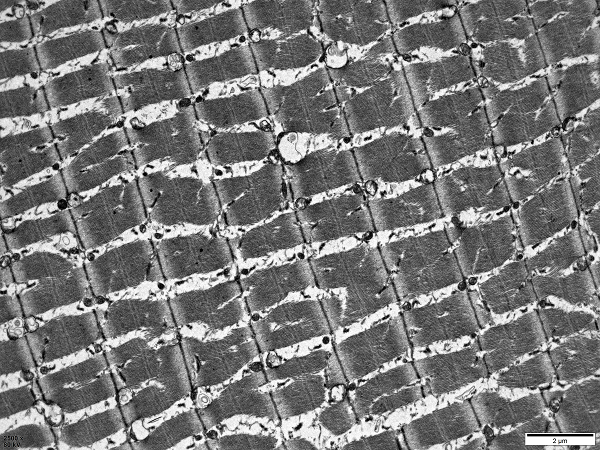

透射電鏡就像是細(xì)胞的“X光機(jī)”,能夠清晰地展示細(xì)胞內(nèi)部的各種結(jié)構(gòu),如細(xì)胞核、線粒體、內(nèi)質(zhì)網(wǎng)等。這些結(jié)構(gòu)對(duì)于研究細(xì)胞的生長、分化和凋亡等過程至關(guān)重要。

細(xì)胞結(jié)構(gòu)觀察

肺透射電鏡觀察